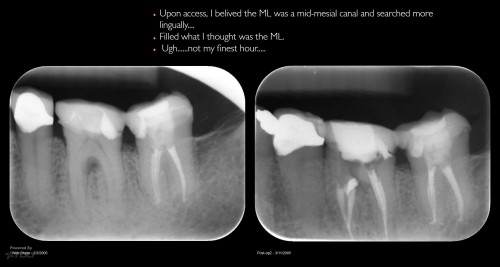

Disappointing recall

Busy recalling cases from the 10-15 yr time frame. Had I just done 5 yr recall, I’d never know …. gbc